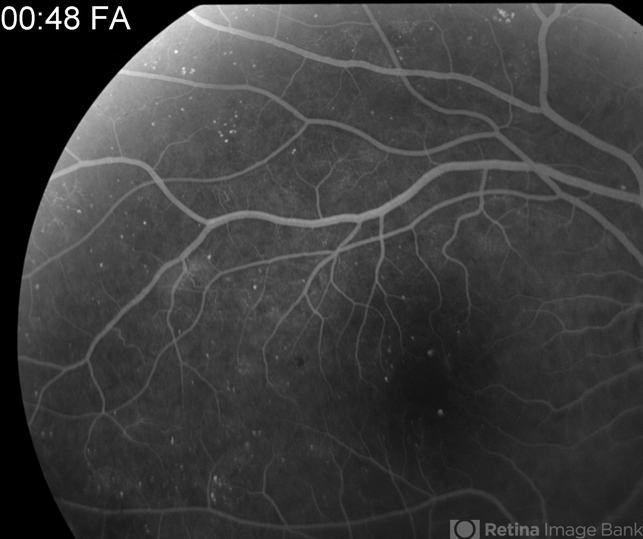

- Proliferative Diabetic Retinopathy with Vitreous Hemorrhage

- vitreous hemorrhage, subhyaloid hemorrhage, cotton wool spots, neovascularization (NV)

- 30 year old diabetic man with proliferative diabetic retinopathy and vitreous hemorrhage